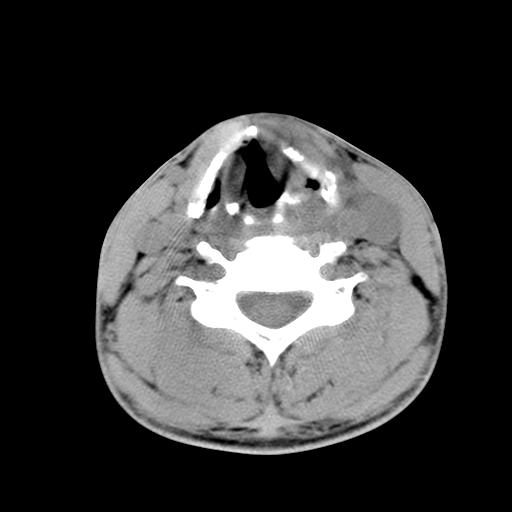

标题: CT15118:f-27y,左颈部肿一个月,无发热、无压痛 [打印本页]

标题: CT15118:f-27y,左颈部肿一个月,无发热、无压痛

1、甲状腺左叶病变:腺瘤?结节性增生?其他?

2、上极周围间隙病变。

3、2者关系?

左侧甲状腺肿大,密度不均.同侧甲状软骨似有破坏(建议传骨窗).左侧颈静脉增粗,各组织之间分界不清,有多个肿大淋巴结.甲状腺肿并感染?临床症状不符.淋巴结核?请结合其他检查.